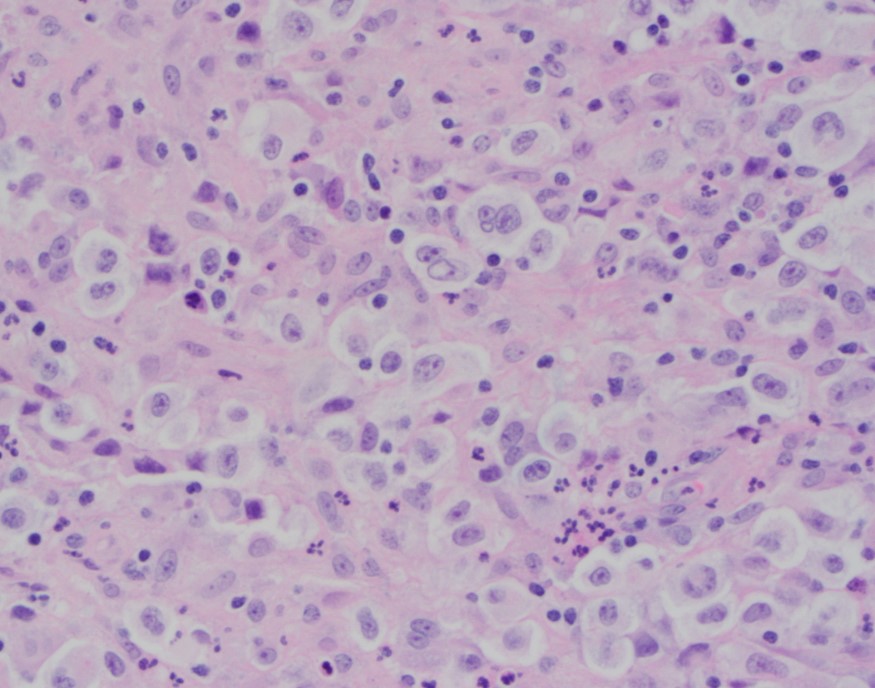

A 23 year old man presented to the hospital with recurrent fever up to 103F with associated nausea and vomiting, epistaxis, watery diarrhea, dyspnea, and decreased appetite for several days. Blood cultures from admission were positive for MSSA and a stool PCR was positive for Vibrio species. He was admitted and treated for sepsis. His CBC demonstrated a marked pancytopenia ( WBC count 0.6 K/μL) and the hematopathology team was consulted to review the peripheral blood film.

Review of the peripheral blood confirmed a markedly pancytopenic picture with virtually no leukocytes in the region of best RBC “spread” (Image 1A). In the periphery of the smear (1B and C) clusters of leukocytes were noted where left-shifted granulocytes were seen. Many demonstrated nuclear irregularity and abnormal granulation (B) and some showed the presence of numerous Auer rods (Image 1C, arrows).

The presence of abnormally granulated immature neutrophilic precursors, and cells with numerous Auer rods was morphologically compatible with acute promyelocytic leukemia (APL) and a rush preliminary diagnosis was rendered. The patient was started on ATRA therapy and FISH for PML-RARA was expedited.

Two distinct subtypes of APL exist: hypergranular (typical) or microgranular. The hypergranular variant is filled with large Auer rods and with dense cytoplasmic granules that can obstruct the nucleus. In contrast, the microgranular variant has a scantiness of cytoplasmic granules or small azurophilic granules.